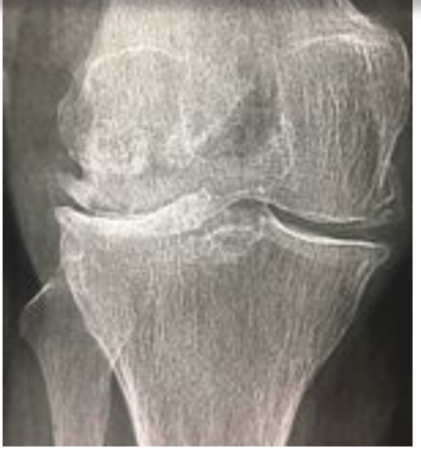

Gonarthrose FT externe

pincement de l’interligne FT externe

Ostéophytes externes